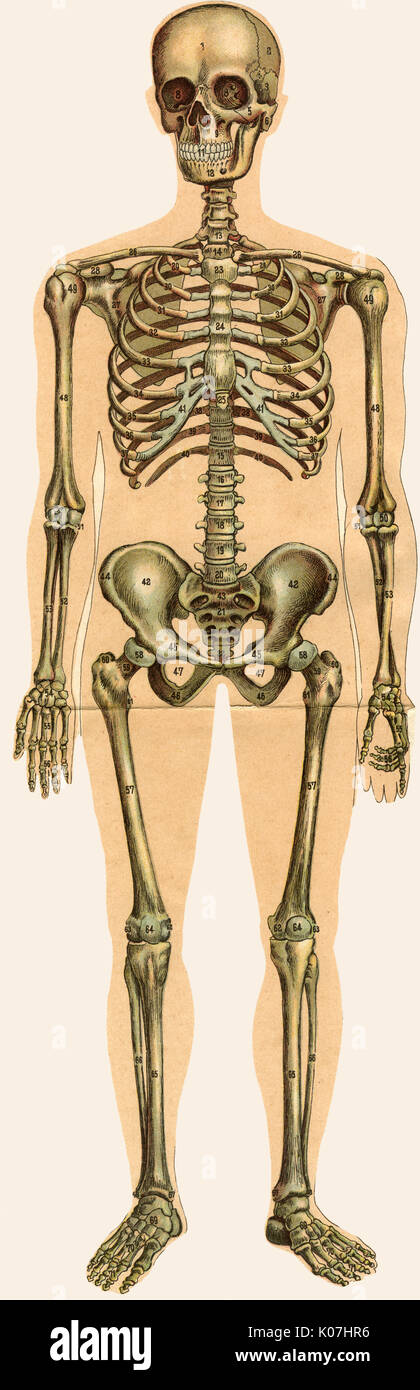

Dépliage de l'anatomie masculine Banque D'Imageshttps://www.alamyimages.fr/image-license-details/?v=1https://www.alamyimages.fr/depliage-de-l-anatomie-masculine-image155060954.html

Dépliage de l'anatomie masculine Banque D'Imageshttps://www.alamyimages.fr/image-license-details/?v=1https://www.alamyimages.fr/depliage-de-l-anatomie-masculine-image155060954.htmlRMK07HR6–Dépliage de l'anatomie masculine

Dépliage de l'anatomie masculine Banque D'Imageshttps://www.alamyimages.fr/image-license-details/?v=1https://www.alamyimages.fr/depliage-de-l-anatomie-masculine-image155060955.html

Dépliage de l'anatomie masculine Banque D'Imageshttps://www.alamyimages.fr/image-license-details/?v=1https://www.alamyimages.fr/depliage-de-l-anatomie-masculine-image155060955.htmlRMK07HR7–Dépliage de l'anatomie masculine